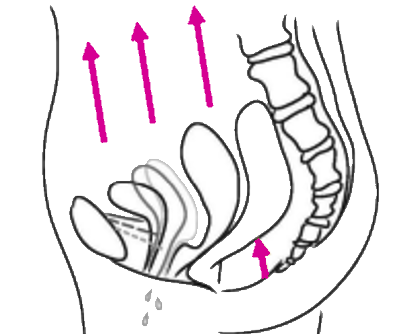

Then, you reprogram the pelvic floor to coactivate with the diaphragm: When you inhale, the pelvic floor extends and relaxes, when you exhale, it lifts and the muscles contract.

It is like training any muscle: contraction and relaxation. So you tone & strengthen the pelvic floor, but also teach it to relax. This means less incontinence, reducing prolapse symptoms, and also less abdominal pain, eg. during period.

The pelvic floor

Responsible for the flexible support of the uterus, the bladder and also the rectum. You will learn how to activate and to relax it, and also physically to lift it. As a consequence, incontinence and prolapses can be reduced, sexual function can improve, period pain can decrease.

After giving birth or during menopause, it is absolutely important to recover the pelvic floor health and maintain it.